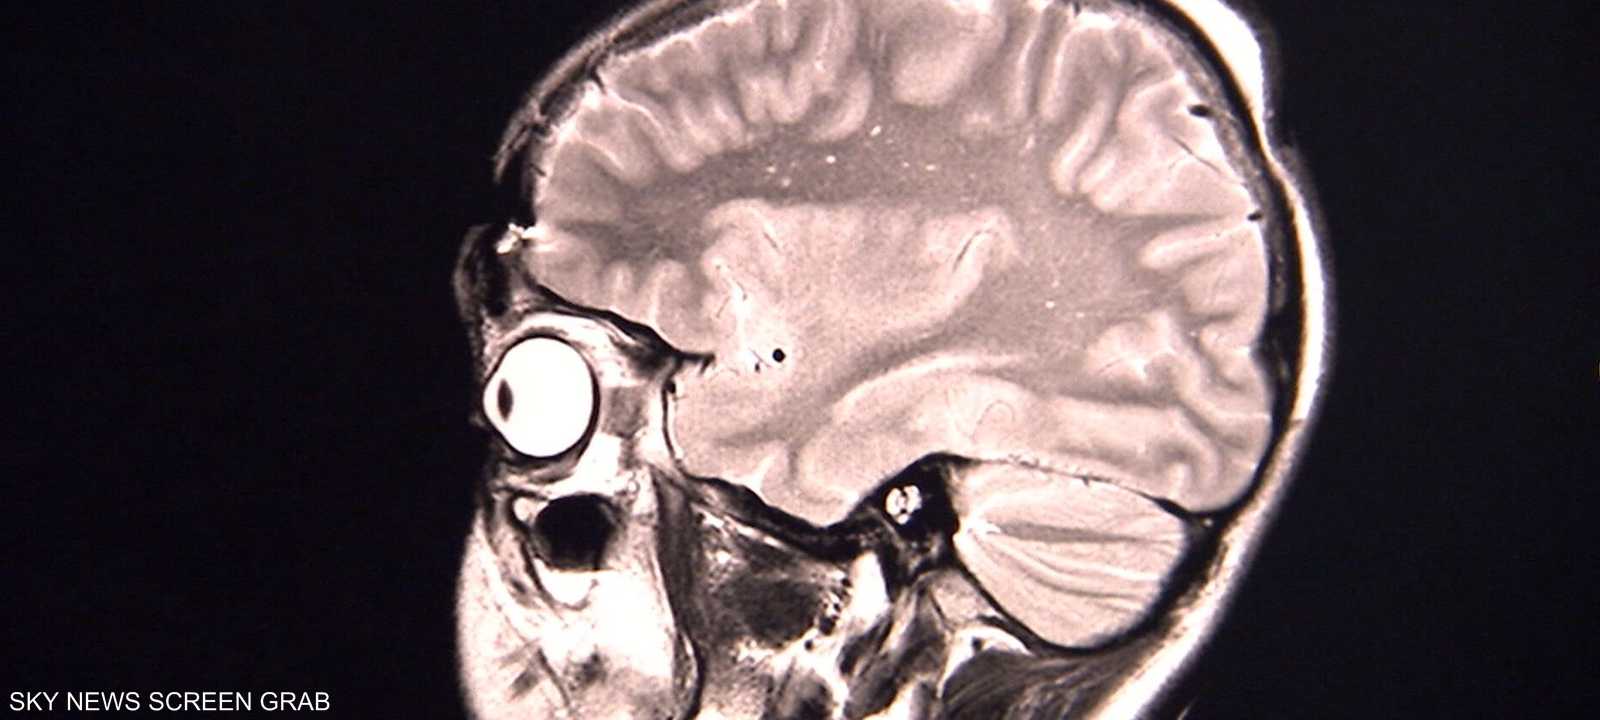

ورغم أن ثلاث حالات ليست كافية للوصول إلى استنتاجات على نطاق واسع بشأن الوباء، إلا أن العلماء يعتقدون أن الأعراض ربما تكون نتيجة للاستجابة المناعية التي تسبب التهابا في أجزاء معينة في الدماغ.